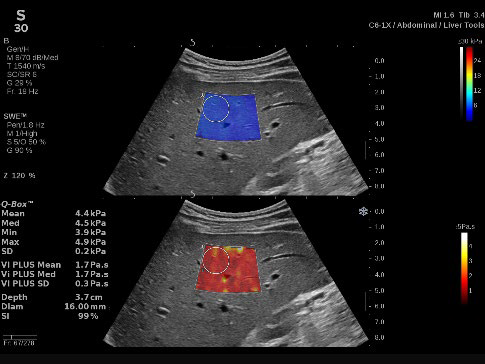

(3)新たに搭載したVi PLUSTM イメージング

肝臓組織の粘性の定量化、弾性率のリアルタイム表示、剪断弾性波伝搬速度のディスパージョン評価を可能にするモードである。(C6-1X プローブ、Liver & Abdomen プリセット、General プリセット使用時)SWE PLUSTM イメージングとVi PLUSTM イメージングは同時リアルタイムに表示される。

肝臓領域の腹部超音波検査において、より精密な情報を提供するVi PLUSTM イメージングを搭載し、肝臓の非侵襲的検査にも対応可能な、次世代モデル。